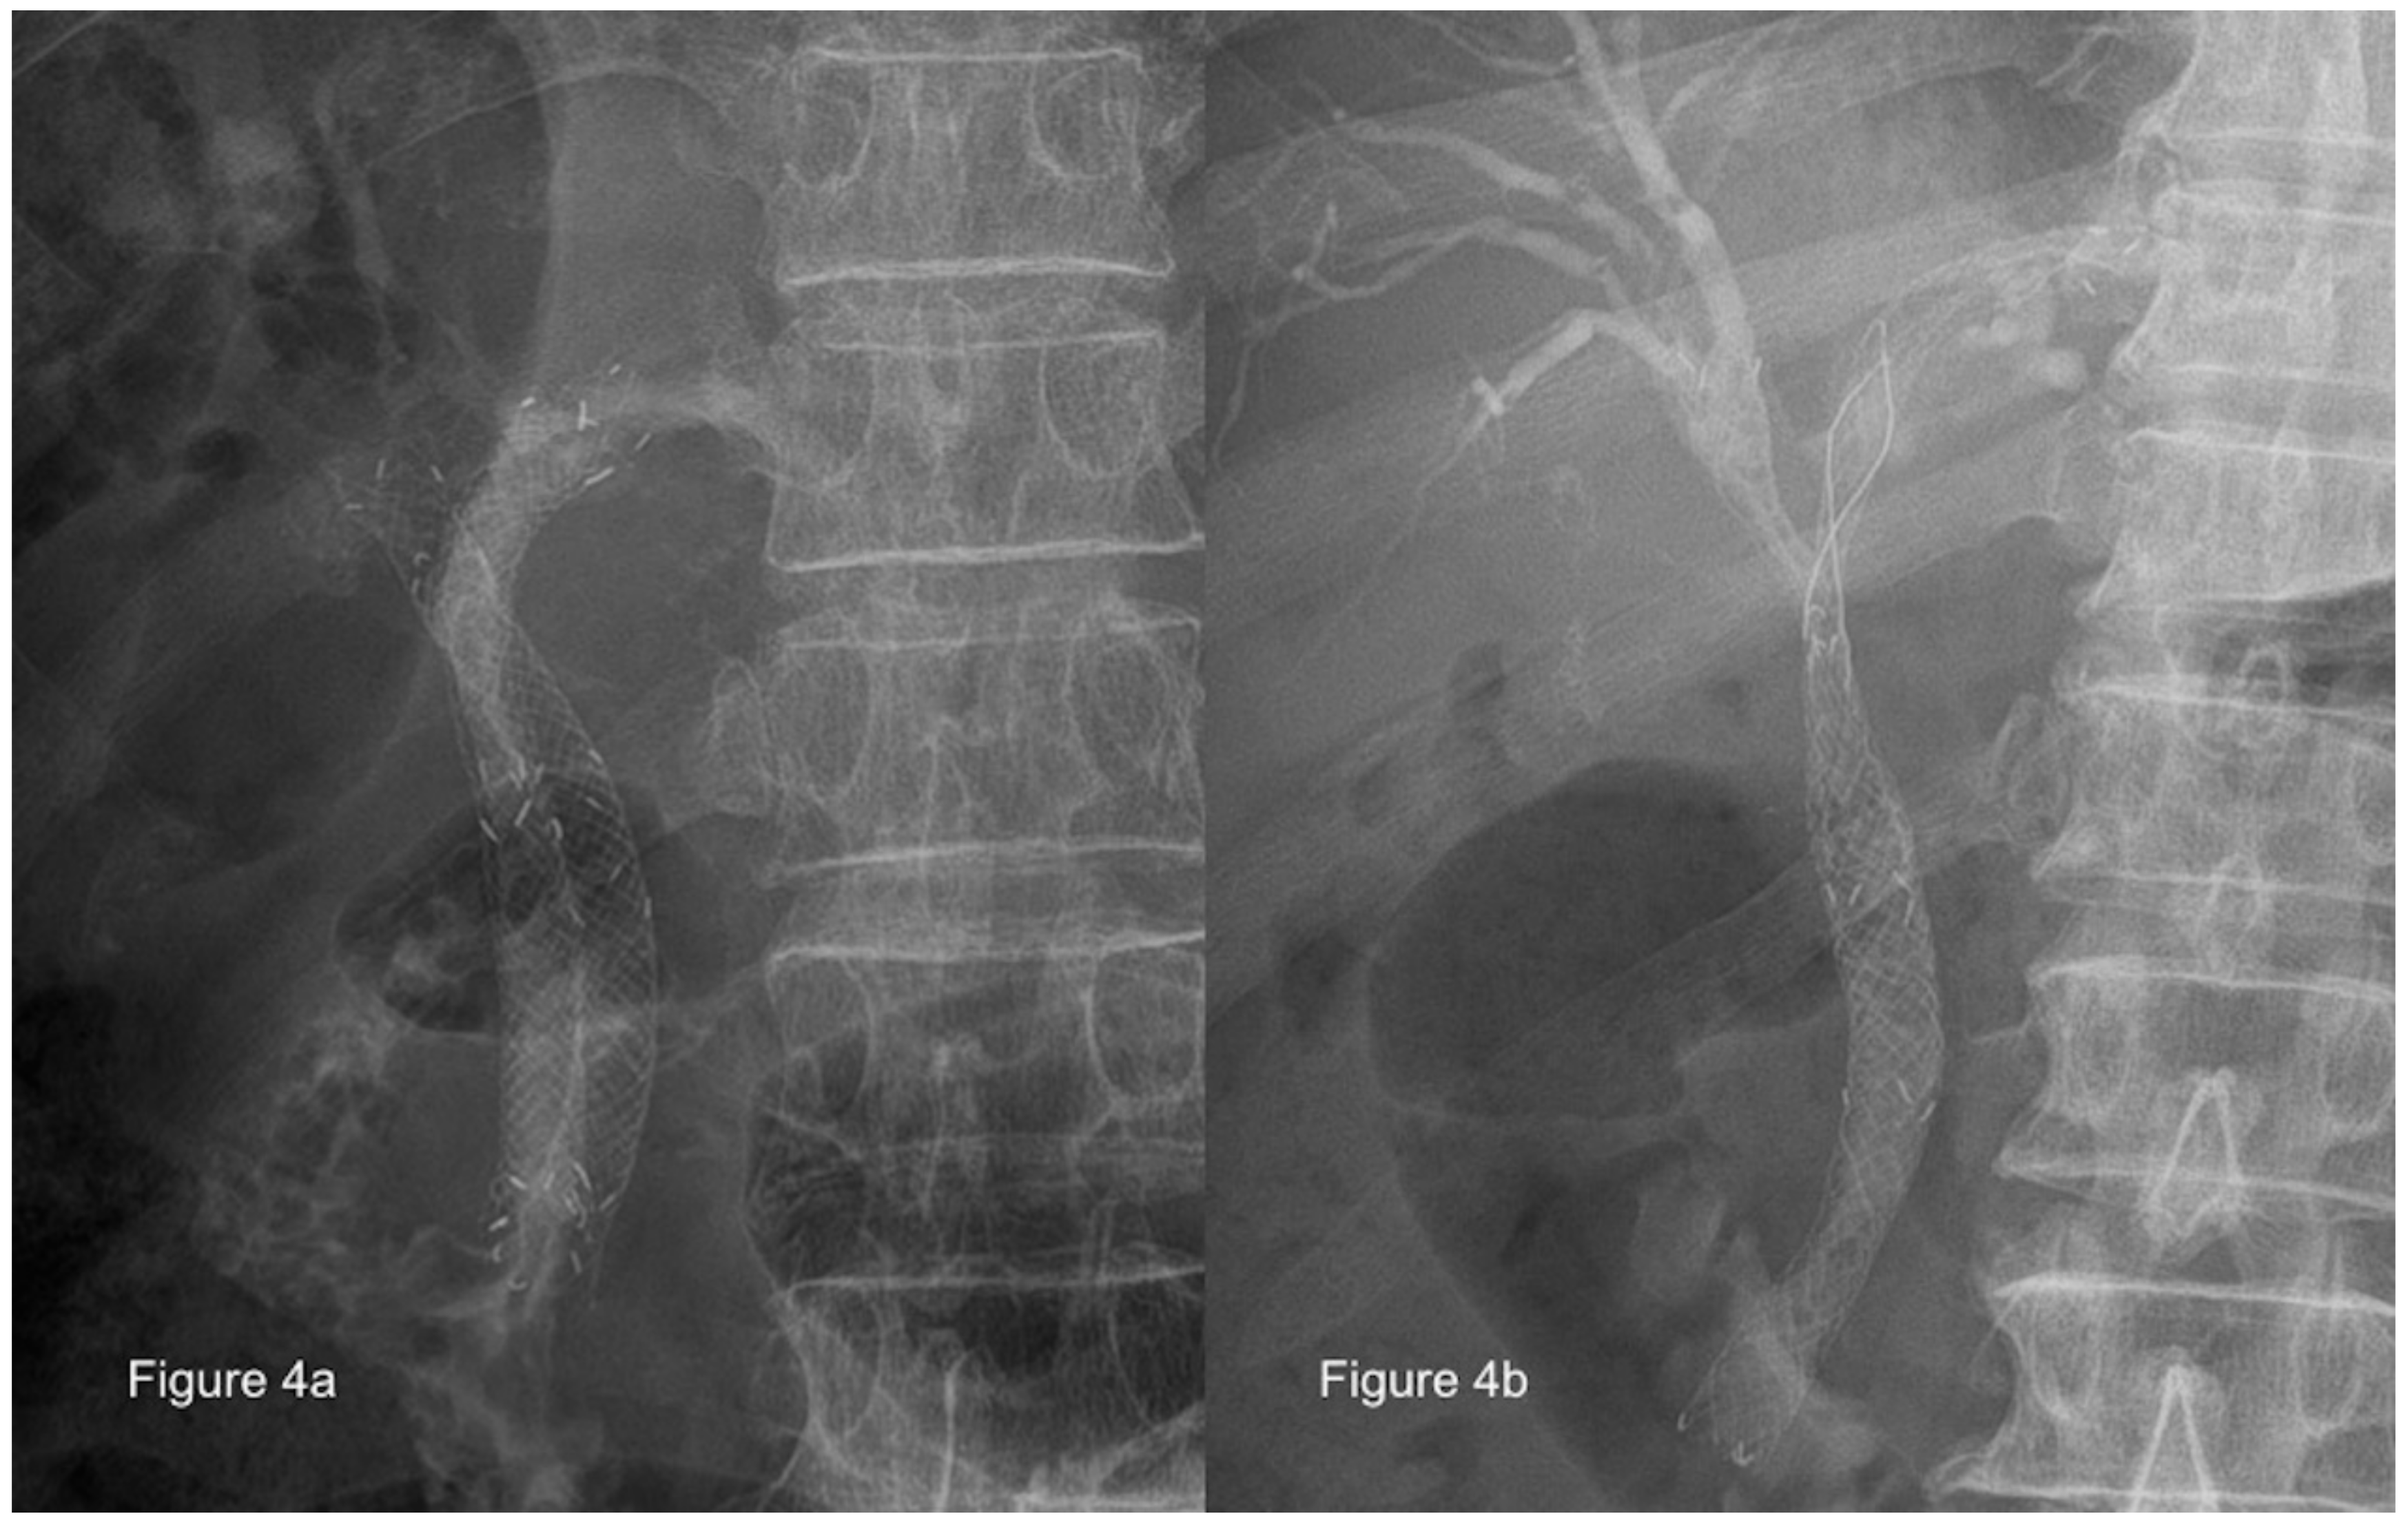

4.3. Rescue Management

- Dowsett, J.F.; Vaira, D.; Hatfield, A.R.; Cairns, S.R.; Polydorou, A.; Frost, R.; Croker, J.; Cotton, P.B.; Russell, R.C.; Mason, R.R. Endoscopic biliary therapy using the combined percutaneous and endoscopic technique. Gastroenterology 1989, 96, 1180–1186. [Google Scholar] [CrossRef]

- Kim, Y.S.; Gupta, K.; Mallery, S.; Li, R.; Kinney, T.; Freeman, M.L. Endoscopic ultrasound rendezvous for bile duct access using a transduodenal approach: Cumulative experience at a single center. A case series. Endoscopy 2010, 42, 496–502. [Google Scholar] [CrossRef] [PubMed]

- Dhir, V.; Bhandari, S.; Bapat, M.; Maydeo, A. Comparison of EUS-guided rendezvous and precut papillotomy techniques for biliary access (with videos). Gastrointest. Endosc. 2012, 75, 354–359. [Google Scholar] [CrossRef] [PubMed]

- Will, U.; Thieme, A.; Fueldner, F.; Gerlach, R.; Wanzar, I.; Meyer, F. Treatment of biliary obstruction in selected patients by endoscopic ultrasonography (EUS)-guided transluminal biliary drainage. Endoscopy 2007, 39, 292–295. [Google Scholar] [CrossRef]

- Park, D.H.; Song, T.J.; Eum, J.; Moon, S.H.; Lee, S.S.; Seo, D.W.; Lee, S.K.; Kim, M.H. EUS-guided hepaticogastrostomy with a fully covered metal stent as the biliary diversion technique for an occluded biliary metal stent after a failed ERCP (with videos). Gastrointest. Endosc. 2010, 71, 413–419. [Google Scholar] [CrossRef]

- Komaki, T.; Kitano, M.; Sakamoto, H.; Kudo, M. Endoscopic ultrasonography-guided biliary drainage: Evaluation of a choledochoduodenostomy technique. Pancreatology 2011, 11 (Suppl. 2), 47–51. [Google Scholar] [CrossRef]